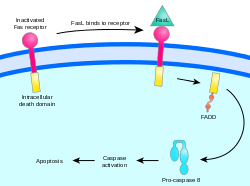

Two theories of the direct initiation of apoptotic mechanisms in mammals have been suggested: the TNF-induced (tumour necrosis factor) model and the Fas-Fas ligand-mediated model, both involving receptors of the TNF receptor (TNFR) family[31] coupled to extrinsic signals.

Fas path

The fas receptor First apoptosis signal (fas) – (also known as Apo-1 or CD95) binds the Fas ligand (FasL), a transmembrane protein part of the TNF family.[31] The interaction between Fas and FasL results in the formation of the death-inducing signaling complex (DISC), which contains the FADD, caspase-8 and caspase-10. In some types of cells (type I), processed caspase-8 directly activates other members of the caspase family, and triggers the execution of apoptosis of the cell. In other types of cells (type II), the Fas-DISC starts a feedback loop that spirals into increasing release of proapoptotic factors from mitochondria and the amplified activation of caspase-8.[35]